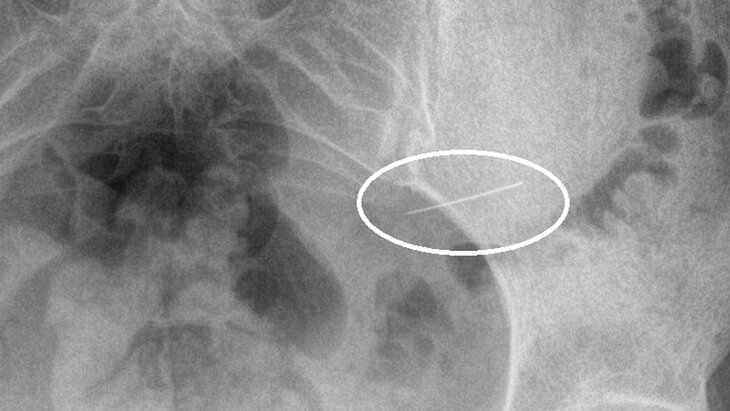

Врачи Красногорской больницы спасли девушку, которая случайно проглотила швейную иглу. Об этом сообщает пресс-служба подмосковного Минздрава.

Девушка обратилась за медпомощью сразу после случившегося. Врачи сделали пациентке рентген, благодаря которому было установлено, что игла находится в желудке. В результате инородный предмет был вытащен с помощью эндоскопического оборудования.